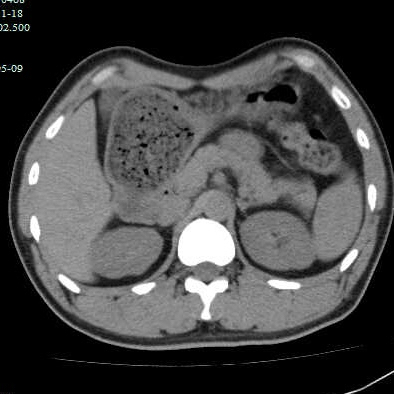

第二个病例,青年男性,也是突然腹痛,症状和第一个类似,首选腹部CT。

胃镜证实

同样治疗后痊愈出院